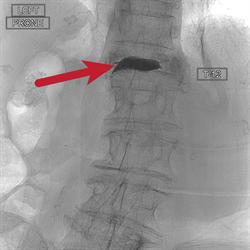

«En cuanto a los análisis, se puede ver que el hueso se había derrumbado en pedazos», dijoPer-Lennart Westesson, MD, DDS, PhD, un neurorradiólogo, que colaboró ​​con el cirujano ortopedista Susan V. Bukata, MD, y B. Freda Hannafon, FNP-C, MSN, del Centro para la salud ósea, para atender a DiGennaro.

Después de varias semanas de estar en cama con dolor de espalda, de la familia DiGennaroestá preocupado de que nunca se recuperaría. Se buscó la ayuda de Bukata, quien sugirió la cifoplastia con balón. El procedimiento consiste en inyectar cemento óseo directamente en lafractura por compresión y el uso de globos para cambiar la parte de atrás las vértebras en su lugar para aliviar el dolor y acelerar la curación.

Este procedimiento ha sido utilizado durante décadas por los médicos de Ortopedia,Neurocirugía y Radiología Intervencionista. Bukata reconoció que la cirugía tradicional con anestesia general no puede ser mejor para DiGennaro, ya que puede elevar el riesgo de accidente cerebrovascular en pacientes ancianos. Bukata sugerido Westesson realizar la cifoplastia con sedación en una sala de radiología intervencionista, en lugar de una sala de operaciones.